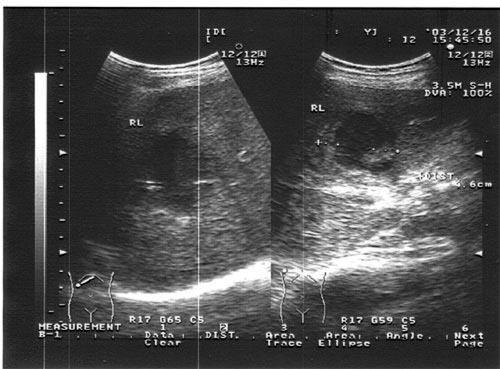

患者,男,高热,右上腹痛,肝区扣击痛。结合超声声像图,诊断为?(?)A.肝血管瘤B.肝脓肿C.肝癌D.脂肪肝E.肝囊肿

问题 患者,男,高热,右上腹痛,肝区扣击痛。结合超声声像图,诊断为?(?)

选项 A.肝血管瘤 B.肝脓肿 C.肝癌 D.脂肪肝 E.肝囊肿

答案 B